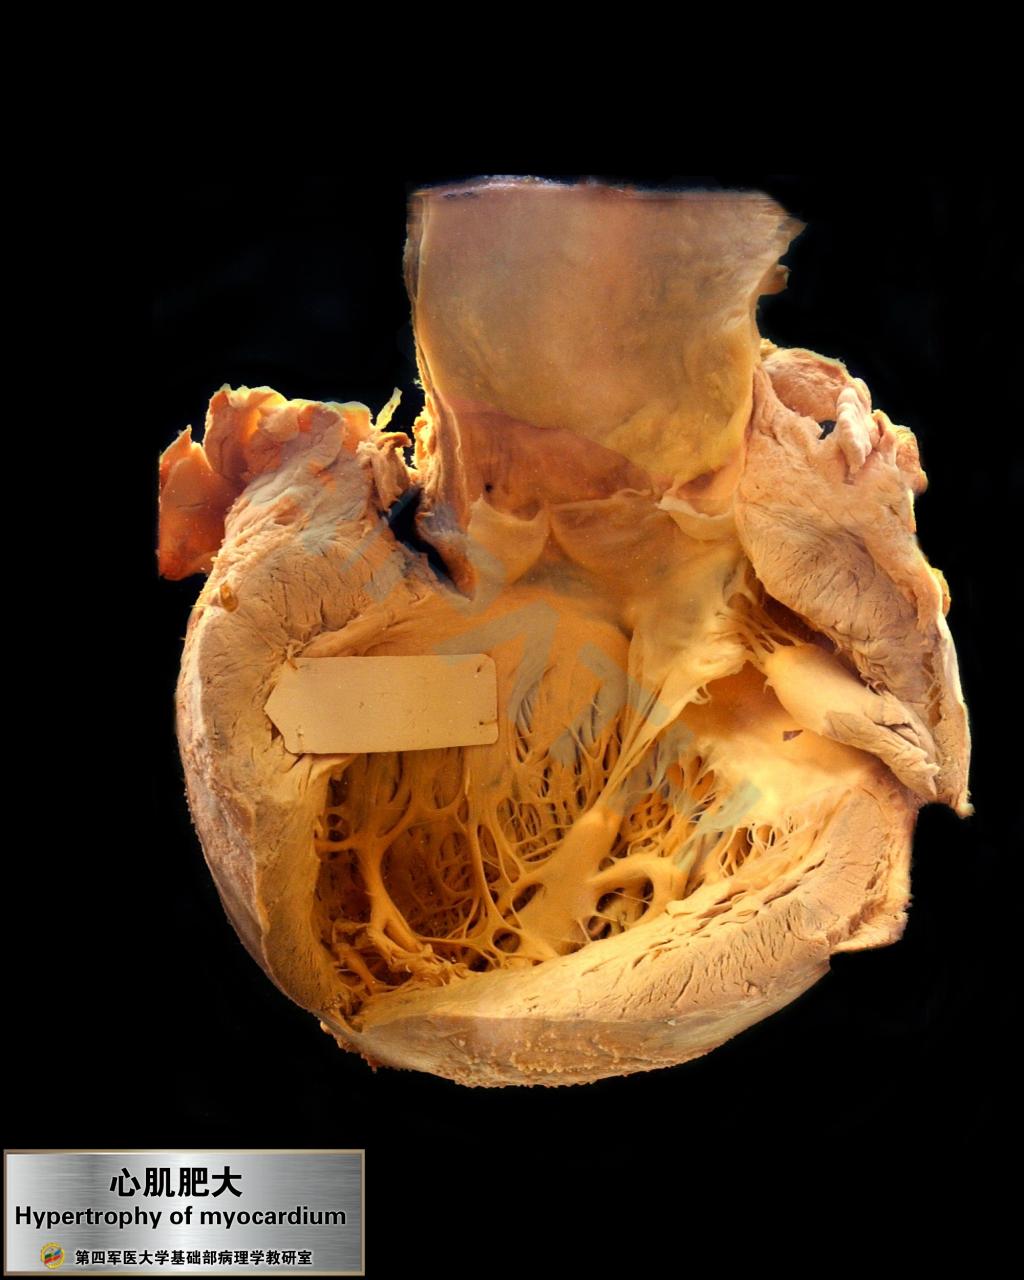

心血管系统疾病

心肌肥大